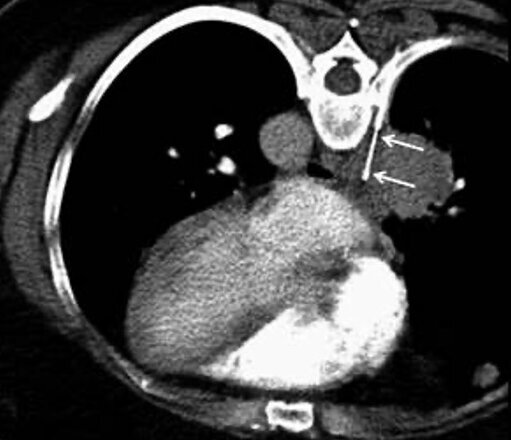

Mittels CT-gesteuerter Punktionen sind wir in der Klinik für Diagnostische und Interventionelle Radiologie am UKS in der Lage, Gewebeproben zur Untersuchung von Tumoren zu gewinnen. Die Punktion erfolgt dabei mittels einer sehr feinen Nadel, sodass selbst kleinste Proben aus Organen oder anderen Bereichen ohne Operation entnommen werden können.